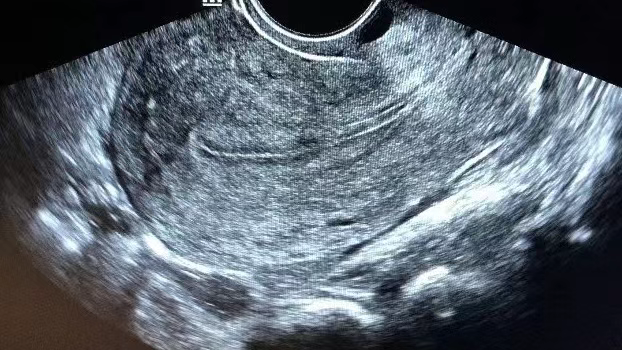

常见于月经第11-14天(接近于排卵期时或排卵后不久),内膜厚度约为9-12mm,超声下的表现为回声均匀但三线模糊。

在这一阶段,雌激素水平持续升高,同时孕激素也开始发挥作用。内膜腺体进一步增长、弯曲,分泌活动逐渐增强,间质更加疏松水肿。

虽然 B 型内膜不如 A 型内膜的三线征明显,但它同样具备较好的容受性,能够为胚胎着床提供相对适宜的环境。

美国试管专家在实际操作中,会综合考虑胚胎质量、患者的个体情况等因素,判断 B 型内膜是否适合进行移植。